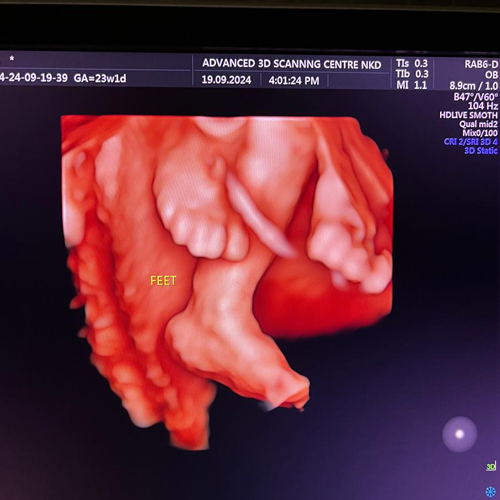

Best Scanning Center In Nakodar